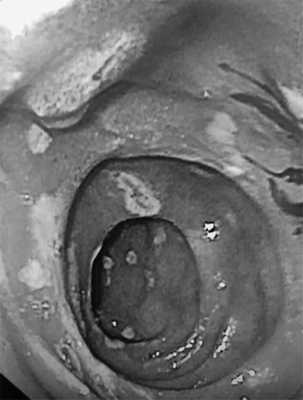

В контрольной ЭГДС №4 (30.08.19) на фоне приема ИПП в двойной дозе вновь зафиксирована отрицательная динамика: увеличение площади эрозий и геморрагий СО желудка, вовлечение в патологический процесс СО пищевода (эрозивный эзофагит степени A по LA) и ДПК (множественные эрозии под фибрином с вкраплением гематина размером 2—5 мм, рис. 1).

Рис. 1. Множественные эрозии двенадцатиперстной кишки под фибрином с вкраплением гематина.